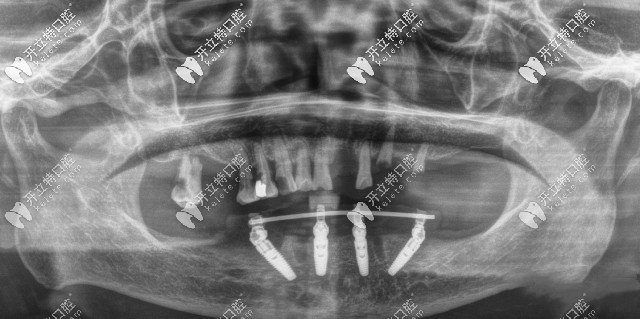

廣州廣大口腔ALLON4半口種植牙CT片

閑話不多說(shuō),大家還是來(lái)親眼見識(shí)一下廣州廣大口腔的種植牙怎么樣吧:

劉國(guó)輝院長(zhǎng)先給我做了檢查,說(shuō)我的牙槽骨情況適合做ALL-ON-4種植牙,而且不用植骨、手術(shù)創(chuàng)傷小、還能省將近一半的費(fèi)用。

難得遇到個(gè)醫(yī)生說(shuō)我不用植骨,又有特價(jià),還考慮啥直接種牙吧!手術(shù)前后僅用了1個(gè)多小時(shí)就,我就重新“長(zhǎng)”出牙齒,成功恢復(fù)半口牙,而且當(dāng)天回家就能吃東西了!